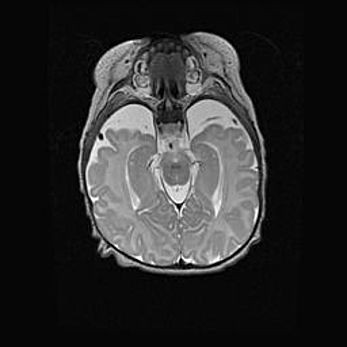

Лейкомаляция с кистозно-глиозной дегенерацией головного мозга.

Возраст: 2 месяца 25 дней

Вес: 6400 г

Окружность головы: 40 см

Срок гестации: 41 неделя

Лейкомаляцию относят к ишемически-гипоксическим повреждениям головного мозга, диагностируемым у новорожденных. При лейкомаляции в головном мозге обнаруживают очаги некроза, возникшие после тяжелой гипоксии и нарушения кровотока. В процессе морфогенеза очаги проходят три стадии: 1) развития некроза, 2) резорбции и 3) формирования глиозного рубца или кисты. Перивентрикулярная лейкомаляция (ПЛ) встречается примерно в 12% случаев среди новорожденных, обычно – у недоношенных детей, причем, частота ее зависит от массы, с которой младенец появился на свет. Наибольшее число малышей страдает лейкомаляцией, если масса при рождении 1500-2500 г.